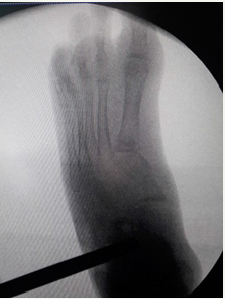

Clinical and Radiographic correction is controlled intraoperatively. The Osteotomy is fixed with rhombic compression staples (Charlotte® Wright). The incision is closed with absorbable suture in planes. If it is necessary, Achilles tenoplasty is performed at the same surgical time (Figure 2).

Figure 3:

Patients were immobilized with plaster short boot for 4 weeks. Plaster windows were made to perform the cures and it was only change (cast) in case of complications or break of it (Figure 3).